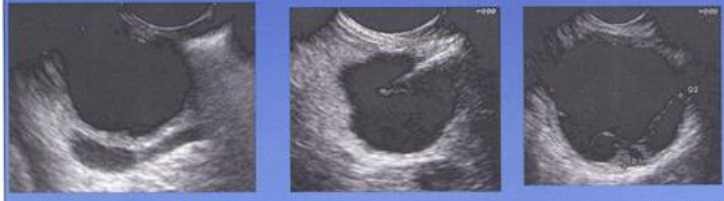

19

Q

מהו הממצא

A

פסאודו-סיצטה, ציסטה שאינה צלולה

**נראה בד”כ אחרי טראומה או דלקת לבלב